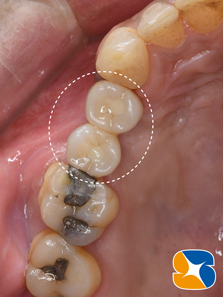

前回の骨の造成手術から6ヶ月後の状態です。とてもふっくらした状態で綺麗に治っています。

いよいよ ここからが本番です。